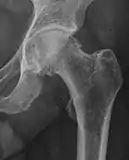

| Femoral head-neck offset | ![]() |

Offset of the femoral head with regard to most prominent aspect of the femora neck | >10 mm |